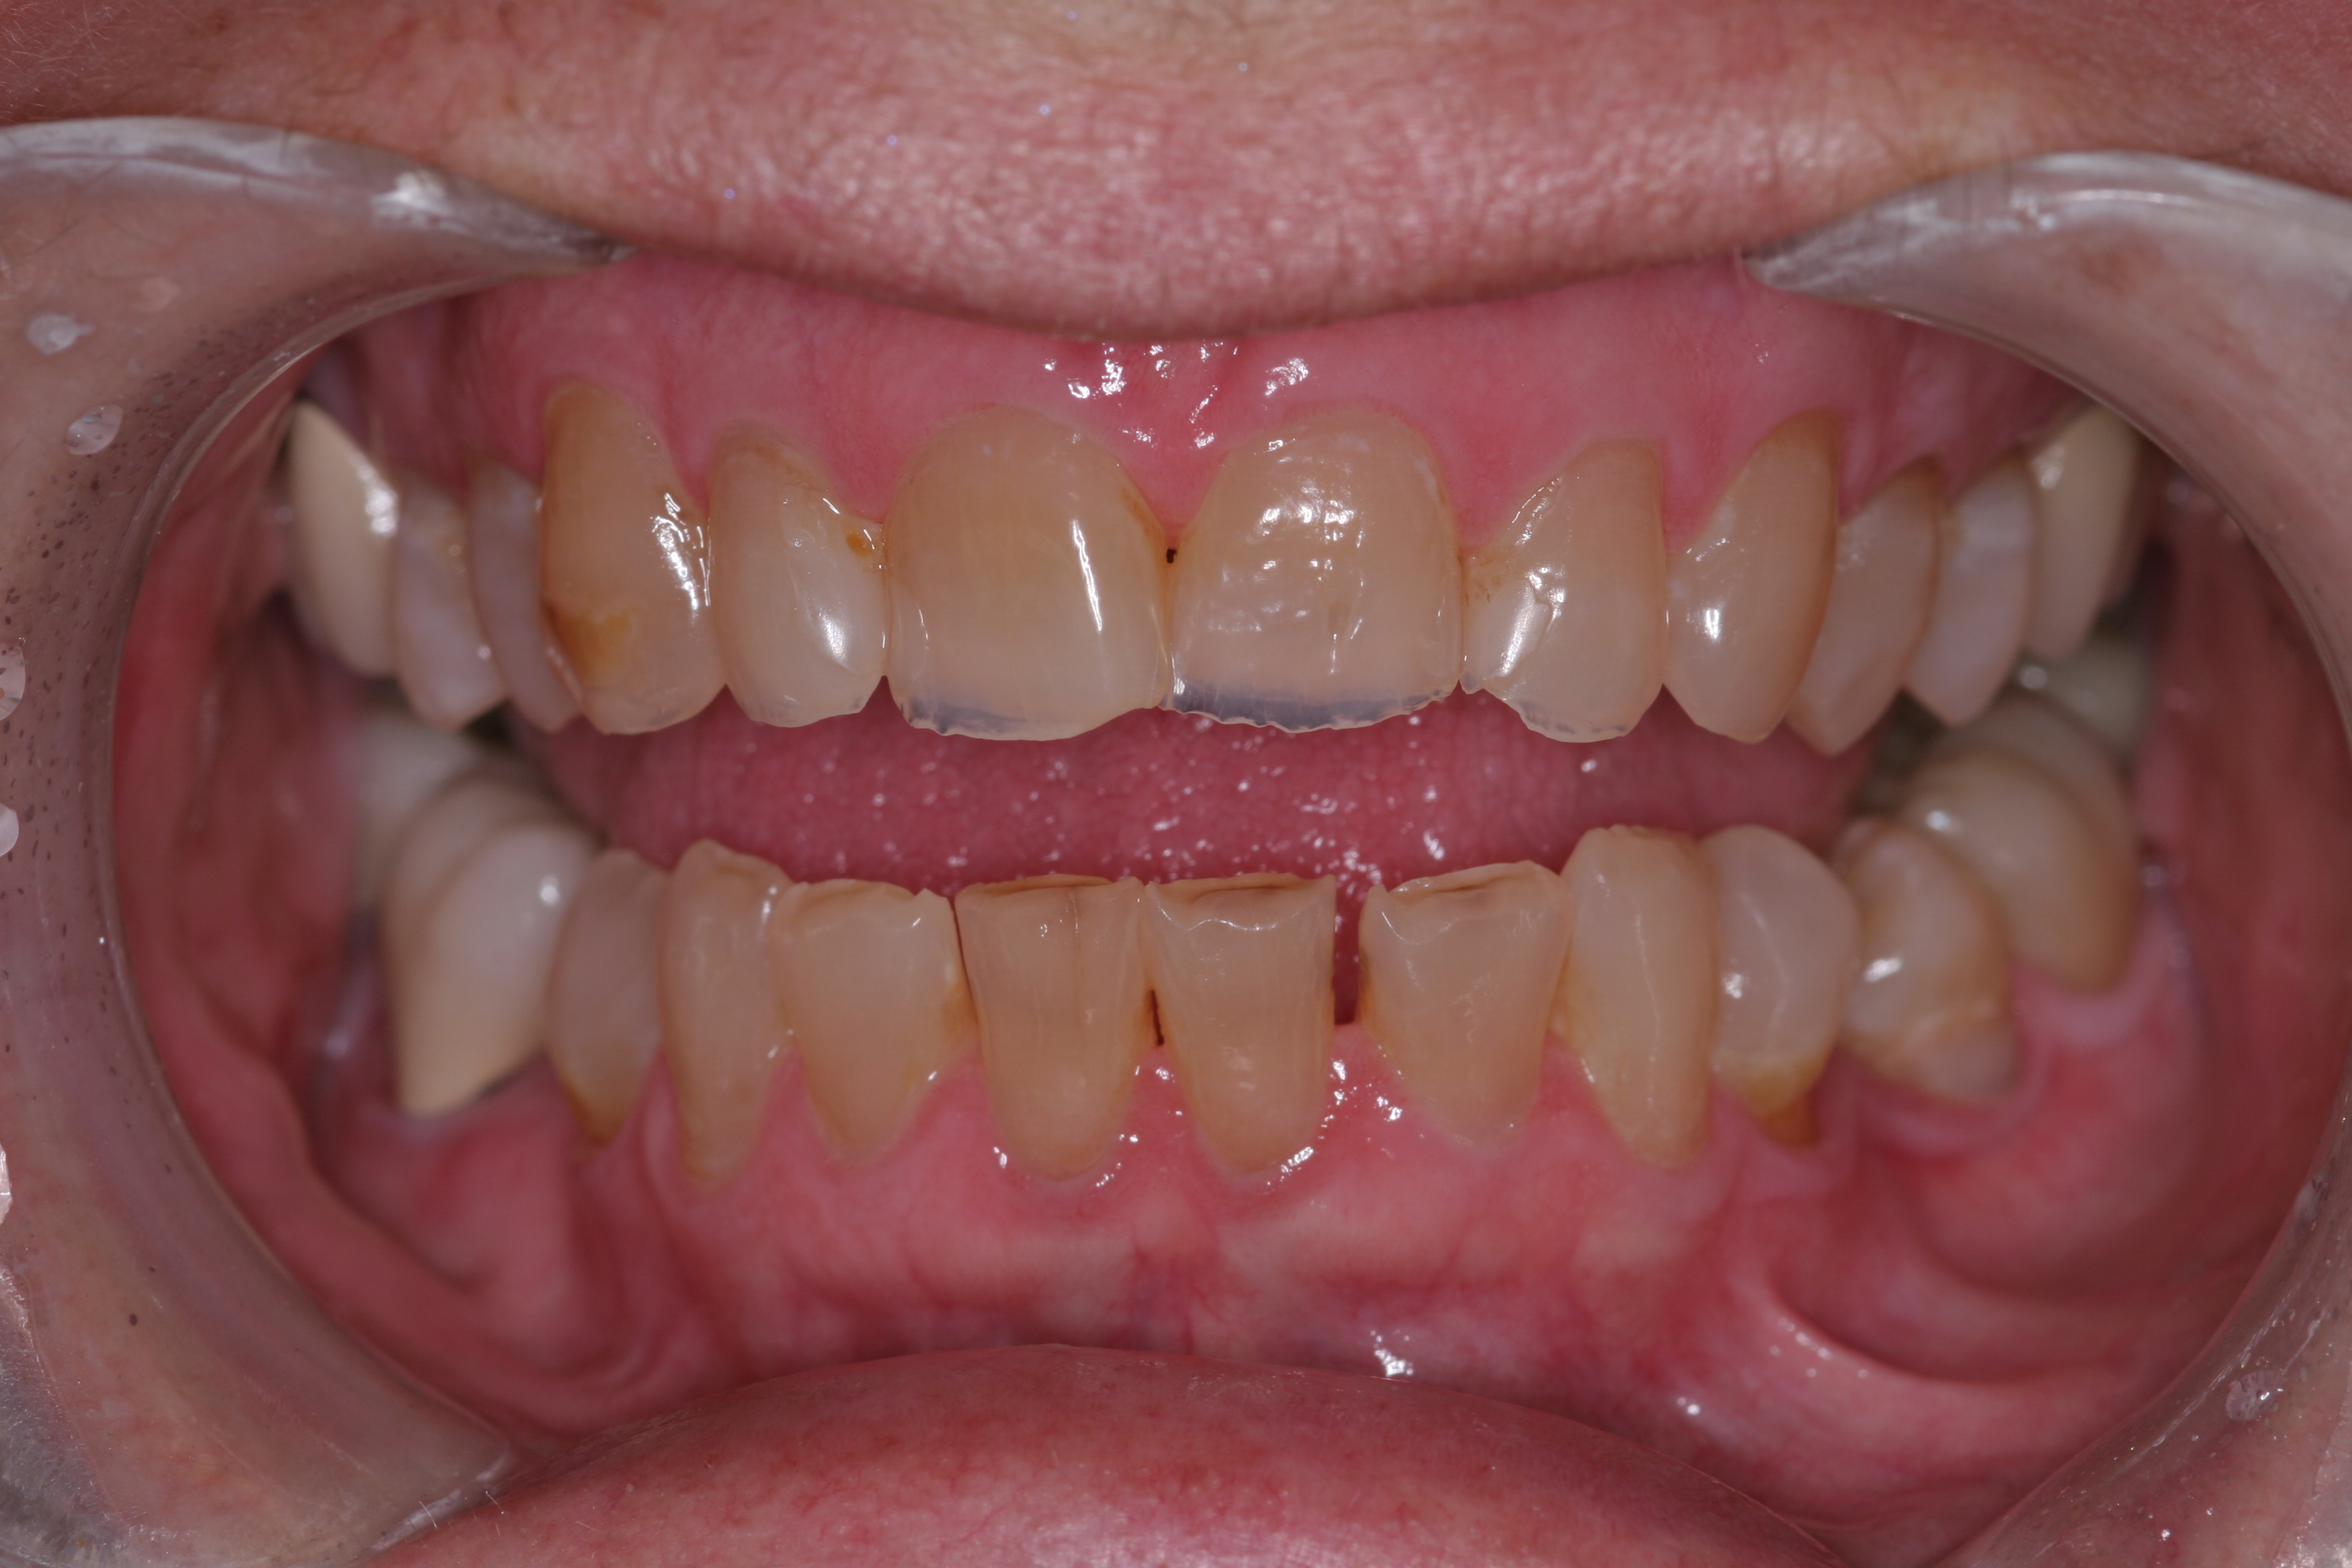

A patient presented with advanced generalized wear of her anterior teeth (Figure 10 and Figure 11). She was displeased with their overall appearance because of their color and wear (Figure 12). A complete examination was performed, revealing instability in her temporomandibular lateral poles bilaterally, sore muscles of mastication, advanced wear, a CR/MIP discrepancy, and loss of her anterior guidance due to the wear. Although the topic is beyond the scope of this article, the patient was also screened for possible sleep apnea. This included an evaluation of the Mallampati score, previous sleep therapy evaluation or treatment, snoring history, an evaluation of her neck size, her weight status, and the presence of the tonsils and their size. In every case, if this clinician suspects airway obstruction to be playing a role in tooth wear issues, the patient is referred to a sleep physician. The patient in this case displayed few apnea risk factors, and the patient’s anterior wear facets fit together like a “lock and key” pattern seen in parafunctional activity. Splint therapy was initiated to stabilize the joints and muscles. A repeatable CR position was verified through load testing. At this point diagnostic models, photographs, a CR bite record, and a facebow were taken and recorded.

(11.) A patient presented with advanced generalized wear of her anterior teeth, and was displeased with their overall appearance because of their color and wear.

Figure 11

(12.) A patient presented with advanced generalized wear of her anterior teeth, and was displeased with their overall appearance because of their color and wear.

Figure 12